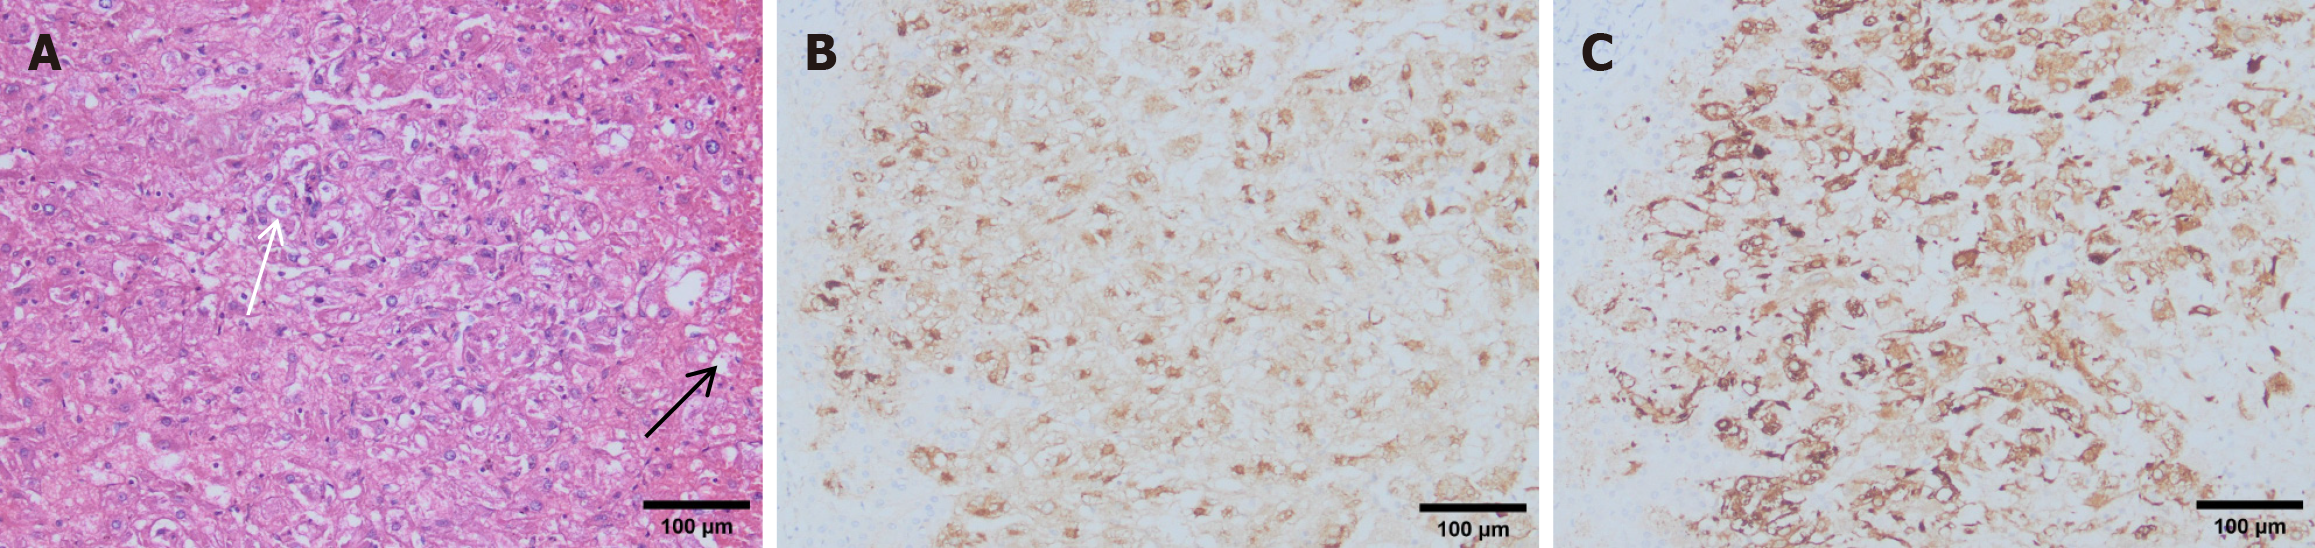

Figure 4 Postoperative pathological findings.

A: Hematoxylin-eosin staining. The tumor cells are polygonal with translucent cytoplasm containing uneven eosinophilic granules. Perinuclear eosinophilic condensation shows a clear appearance (black arrow). The nuclei are round or oval with a distinct nucleolus and sparse chromatin (white arrow); B and C: Immunohistochemical staining revealed positivity for HMB45 (B) and Melan-A (C), with increased expression in both the cytoplasm and nuclei of tumor cells compared to normal liver cells.